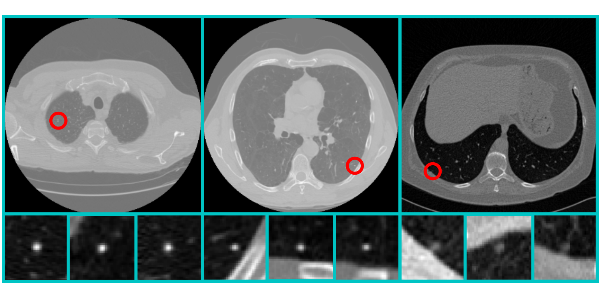

Qualitative results

Figure 1. Qualitative results of high scored nodule detection.